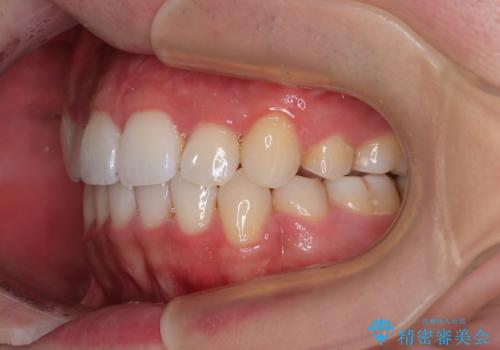

前歯の歯列が整ったことで、歯磨きが大変やりやすくなり、患者様には大変満足していただけました。